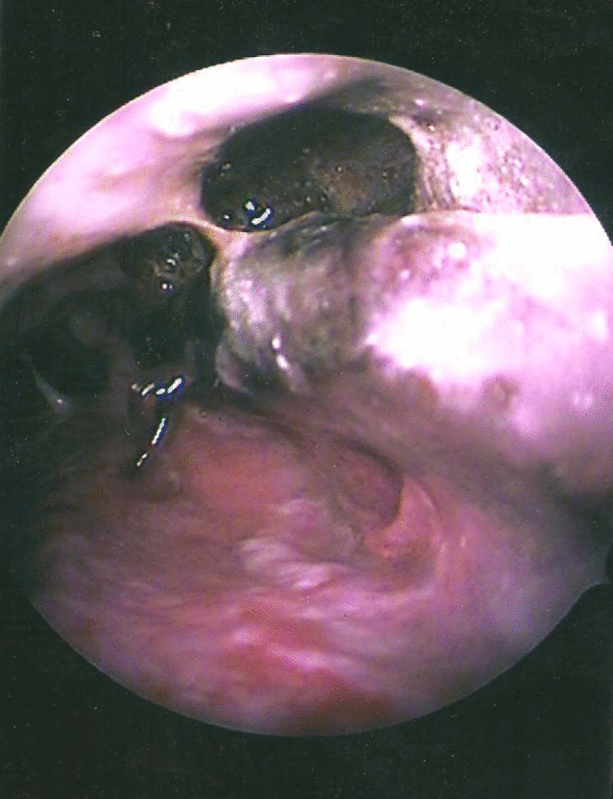

The patients presented with following signs and symptoms: fever (50 %), thick nasal discharge—dark and blood stained (60 %), black necrotic turbinates (50 %), periorbital or facial swelling (40 %), decreased vision (40 %), opthalmoplegia (30 %), palatal ulceration or perforation (10 %), septal perforation (10 %), headache (30 %), oedema of lids (40 %), chemosis (40 %), sinusitis (30 %), facial paralysis (10 %), restricted movements of eyeball (40 %) and confusion (20 %).

Diagnostic nasal endoscopy were done twice weekly to diagnose recurrence of disease, if recurrence was found debridement of necrotic tissue was carried out.

Patients with rhinocerebral mucormycosis usually presents as acute sinusitis with fever, nasal congestion, purulent nasal discharge, headache and facial pain. All sinuses can become involved and spread to adjacent structures such as palate, orbit and brain usually progresses rapidly. The hallmarks of spread of disease beyond the sinuses are tissue necrosis of the palate resulting in palatal eschars, destruction of turbinates, perinasal swelling and cyanosis of the facial skin overlying the involved sinuses.

Black necrotic intranasal or palatal eschar is highly suggestive of the disease but it occurs in only 40–50 % of those affected [11]. Periorbital cellulitis, extra ocular muscle paresis, proptosis and chemosis frequently develop as a result of disease extension into orbit or cavernous sinus. Spread from the sphenoid sinuses to the adjacent cavernous sinus can result in cranial nerve palsies, thrombosis of the sinus and involvement of the carotid artery [12]. Cranial nerves are progressively involved as the infection spread visual loss may develop from central retinal occlusion or direct orbital extension. Intracranial infection may result from spread through the vasculature or contiguous progression through cribriform plate or orbital apex. Hematogenous spread to other organs is rare unless the patient has an underlying malignancy with neutropenia.